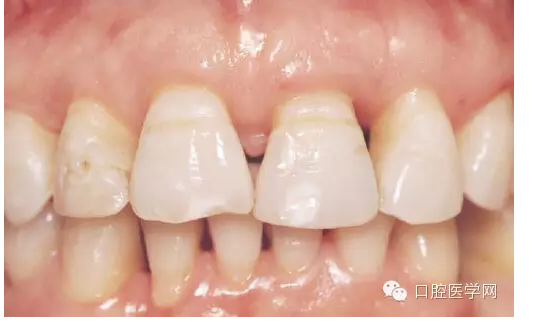

這里先發(fā)一張照片,是一個(gè)需要解決黑三角的病例。照片是在一國外文獻(xiàn)上截的(我很少看國內(nèi)的文獻(xiàn))。從照片上看,患者前牙去區(qū)基本都有黑三角的問題。那么是為什么會(huì)出現(xiàn)黑三角?